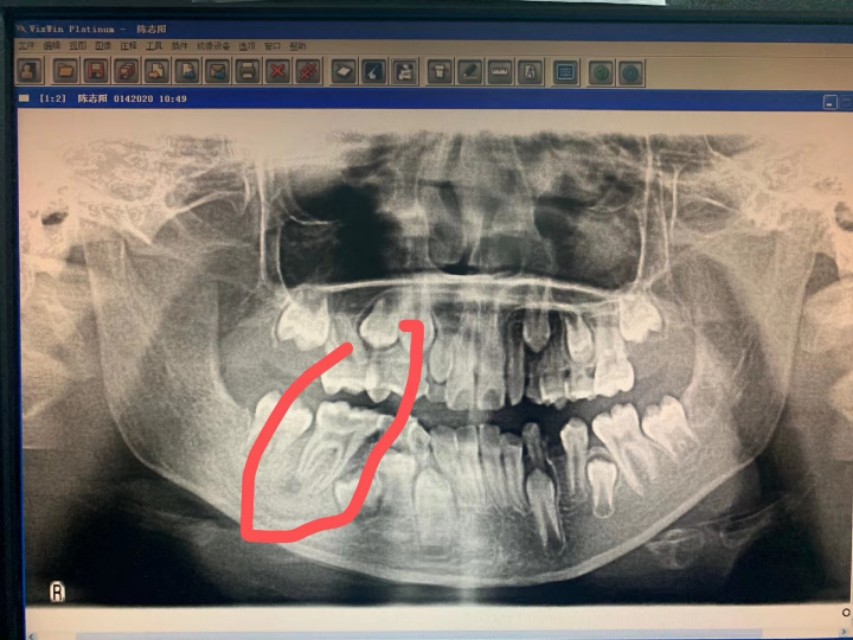

患儿,男性儿童,半年前出现右侧颌面反复流脓,家属半年碾转就诊于数家医院的耳鼻咽喉科和口腔科,多次切开排脓不愈,最后一次在我老师所在科室行全麻瘘管局部清扫手术,自认为手术彻底,谁知10余天后就复发,百思不得其解,复诊时口腔检查,终于发现右下一牙轻微叩痛,(患儿未诉牙自发症状),嘱其再返口腔科就诊,拔除患牙,右颌下瘘管随之而愈,虽然患儿最终得以痊愈,但是过程曲折受尽折磨,患儿的主刀医生已经是头颈外科的顶级专家,依然难免会有差错的时候,行医之路,如履薄冰,特以同道分享!

2、术中未见瘘管,均为肉芽,术后病理亦未报瘘管,只报炎症,未起疑心

3、术中并未见下颌骨皮质受损(是否舌侧可能),排除了牙源性可能